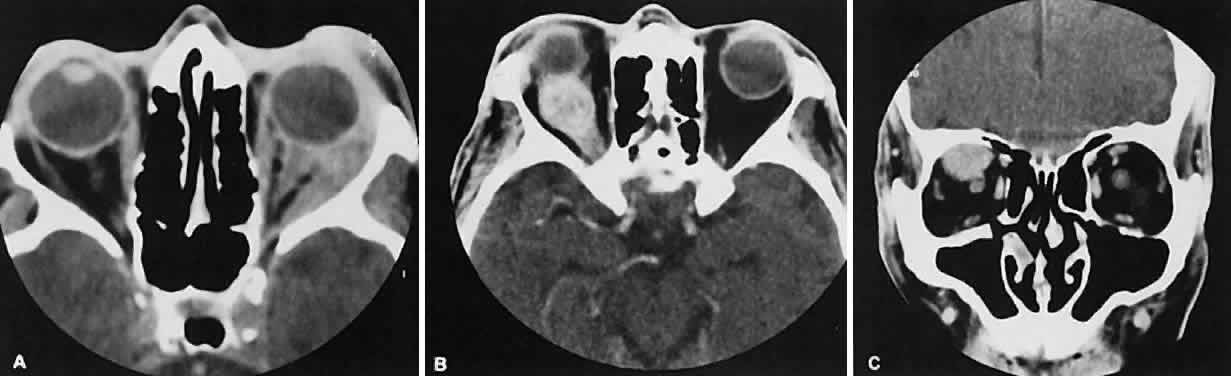

Graves' orbitopathy probably represents the most frequent cause of proptosis and EOM enlargement. The CT findings are fairly stereotyped and typically display various degrees of EOM enlargement (Fig. 7). The inferior rectus muscle usually is affected earliest, followed by the medial rectus, superior rectus, and finally the lateral rectus muscle. Rootman and colleagues13 noted more frequent involvement of the superior rectus/levator and medial rectus muscles than what had been reported previously with Graves' orbitopathy. These muscles can be affected in isolation, with the exception of the lateral rectus. To the best of our knowledge, isolated lateral rectus enlargement has not been reported in Graves' orbitopathy and in our experience usually is associated with a sphenoid wing meningioma.

Fig. 7. Graves' orbitopathy with two variations. Axial (A) and coronal (B) views show symmetric fusiform enlargement of the extraocular muscles with tapered muscle insertions. Note the predominant enlargement of the inferior, medial, and superior rectus muscles with lesser involvement of the lateral rectus muscle, a frequent pattern of enlargement in Graves' orbitopathy. Axial (C) and coronal (D) views of Graves' orbitopathy with expansion of retrobulbar ground substance and relative sparing of the extraocular muscles.

CT evidence of Graves' orbitopathy tends to be bilateral. Approximately 86% of patients with unilateral clinical findings have bilateral CT findings in our experience, which is consistent with the experience of others.42

Morphologically, the EOM belly is enlarged, with a gradual tapering toward and sparing of the tendinous portion of the muscle. Tendon involvement is a typical feature of orbital myositis. Tendon involvement helps to differentiate this lesion from Graves' orbitopathy, although Rootman and Nugent43 have noted a rare patient with Graves' orbitopathy with this finding.